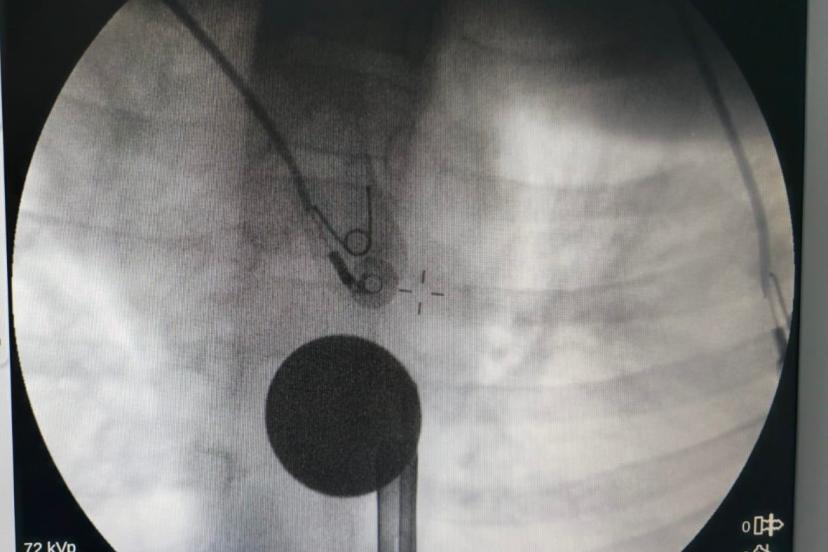

Yabancı cisim yutma şikayetiyle ailesi tarafından Siirt Eğitim ve Araştırma Hastanesine getirilen 8 yaşındaki Y.K., yapılan ilk değerlendirme ve görüntüleme tetkiklerinin ardından ilgili branşlarca operasyona alındı. Y.K.’nın yemek borusuna kadar ilerlediği tespit edilen madeni para, gastroenteroloji uzmanı Dr. Yaren Dirik ve kulak burun boğaz hekimi Yasin Gökçınar tarafından müdahale edilerek çıkartıldı. Operasyonun ardından bir süre gözlem altında tutulan Y.K., tedavisinin tamamlanmasıyla taburcu edildi.

Siirt Eğitim ve Araştırma Hastanesi Başhekim Yardımcısı Uzman Dr. Burak Özkan, çocuk hastalarda yabancı cisim yutma vakalarının ciddi riskler oluşturabileceğini söyledi. Uzm. Dr. Özkan, "Hastanemize başvuran 8 yaşındaki hastamızın yemek borusuna kaçan madeni para, gastroenteroloji ve KBB ekiplerimizin koordineli ve titiz çalışmasıyla herhangi bir komplikasyona yol açmadan başarılı bir şekilde çıkarılmıştır. Operasyon süreci sorunsuz geçmiş olup hastamızın genel durumu iyidir" dedi.